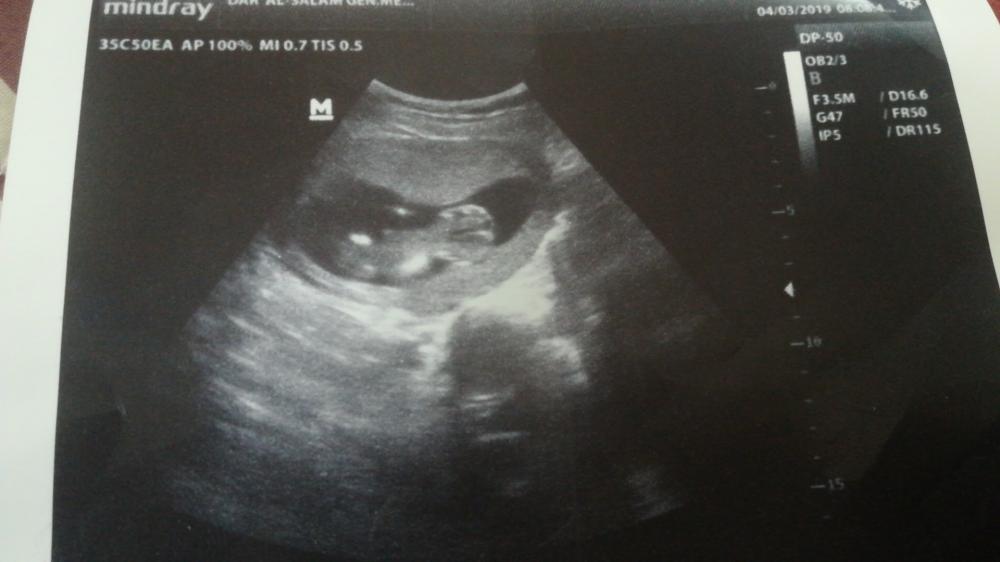

الحمل والإنجاب

اعرفي اعراض الحمل، متابعة شهور الحمل، تمارين الحمل، اعراض الولادة ، اصول الرضاعة الطبيعية